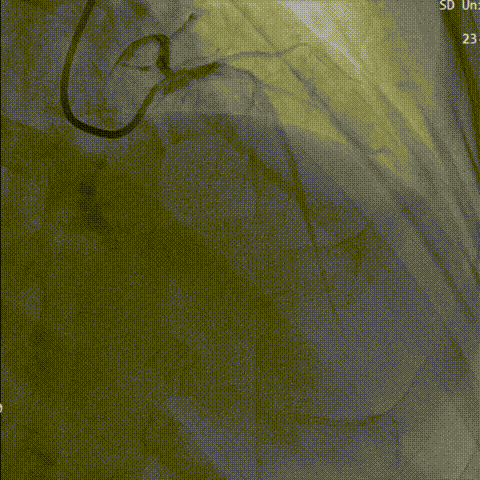

术前先行冠脉造影,回旋支中段狭窄,右冠未见明显异常。

左冠造影

右冠造影

行主动脉根部造影,猪尾确定选择最佳释放体位,观察瓣叶活动,确认是否合并反流,选择合适体位跨瓣。

主动脉根部造影